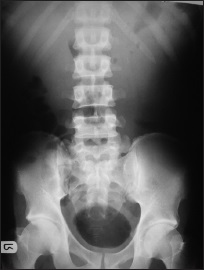

Baseline chest radiographic features among antiretroviral therapy naïve human immuno-deficiency virus positive children in a pediatric care program

Dr. Omolola M. Atalabi, Regina Oladokun, Babatunde Adedokun, Millicent O Obajimi, Kikelomo Osinusi (Author)